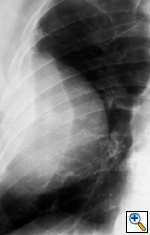

Fig. 13a: Posterior-anterior chest radiograph shows a large peripheral cancer in the right lung with rib destruction, T3.